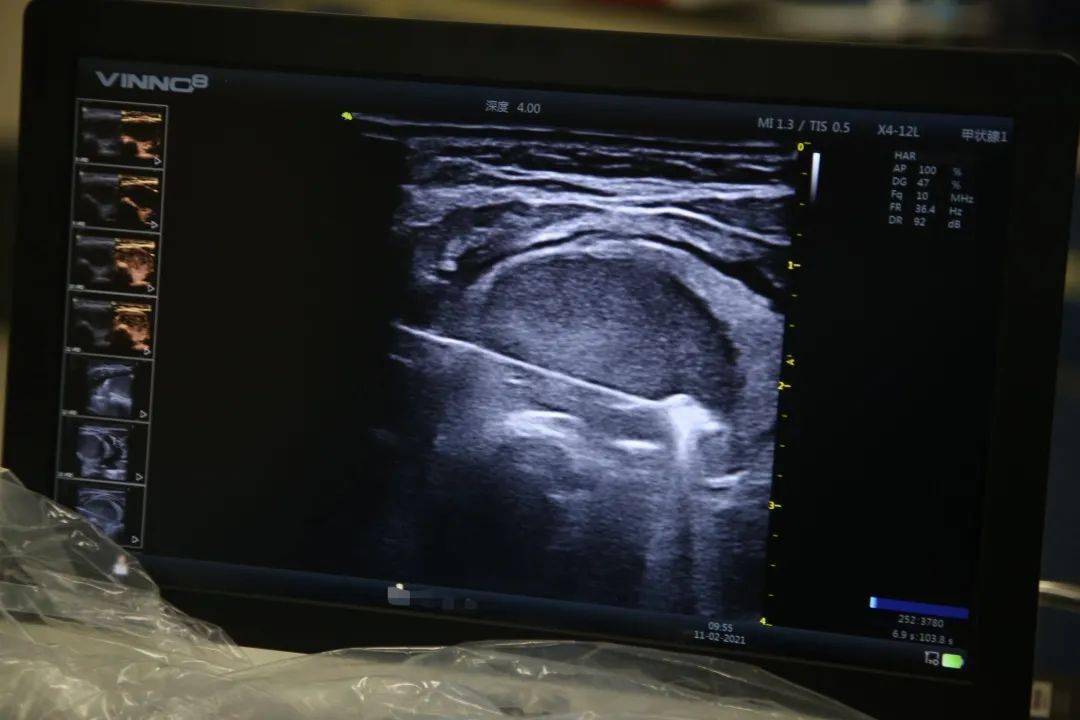

在超声引导下 , 护士将超声造影剂注入患者体内 , 超声图像上很快出现了许微气泡 , 结节的轮廓和内部结构就在造影剂的作用下显示得更清晰了 , 这为后续的微波消融治疗提升了准确性 。

接着 , 赵文鹏医生为患者进行了水隔离的操作——在甲状腺结节与颈前肌群、颈动静脉间注入一定量的生理盐水 。 这一步非常重要 , 要知道 , 热消融的原理是将直径约1mm的微波针植入到病灶内部 , 和微波炉工作原理类似 , 针尖处产生的微波场能使周围组织内的分子、离子发生震荡摩擦 , 导致局部组织温度升高(约130-150℃) , 从而造成结节的不可逆坏死 。 而水隔离这一步可以保护甲状腺结节周围组织不受高温的损害 。 从超声仪的图像上可以清晰看到 , 注入生理盐水后 , 液体把周围肌肉、血管和甲状腺结节隔离开来 , 有效避免了术中的风险 。

在超声图像上 , 可以明显看到 , 一根长长的细针刺进结节内部 。 赵文鹏医生左手拿微波针熟练地由深及浅、由点到面、由面到体逐点进行消融 , 右手拿着超声探头实时扫描观察针尖位置及结节内的变化 , 左脚踩着踏板 , 控制着消融针头周围热场的变化 。